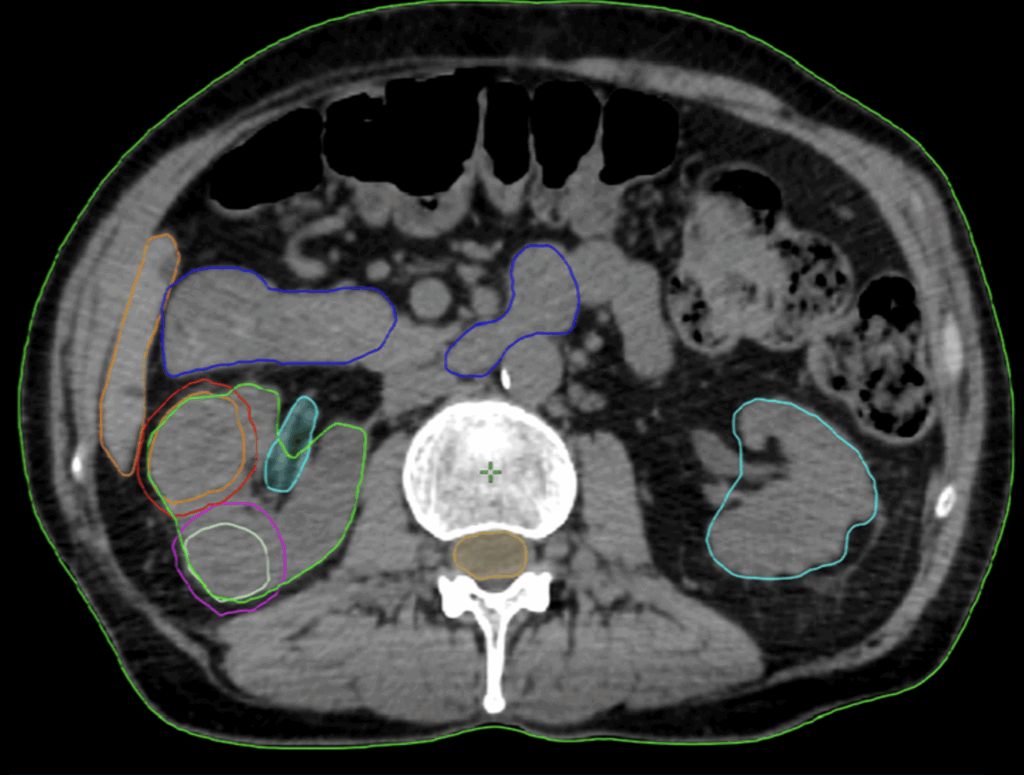

Organs at RiskSmall bowel, stomach, spinal cord, liver, contralateral kidney (figure 2)

Figure 2: Delineation of the GTVs and OARs on the planning CT scan